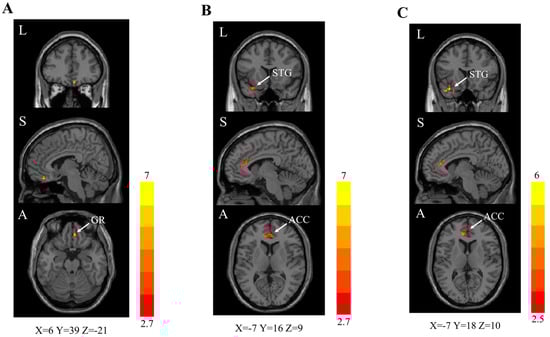

| Olfactory Cortical Network Regions | Cluster Size | Peak z Value |

|---|---|---|

| Combination group vs. standard care group | ||

| Right gyrus rectus | 21 | 6.4 |

| Combination group vs. control group | ||

| Left anterior cingulate cortex | 38 | 5.0 |

| Right anterior cingulate cortex | 7 | 4.2 |

| Left superior temporal gyrus | 28 | 5.2 |

| Standard care group vs. control group | ||

| Left anterior cingulate cortex | 24 | 4.8 |

| Left superior temporal gyrus | 20 | 6.0 |